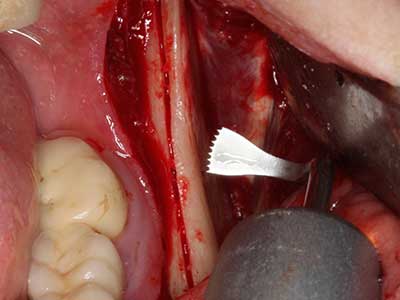

Когато се извършват хирургични процедури върху кост в непосредствена близост до чувствителни структури като кръвоносни съдове или нерви, ротиращите инструменти създават значителен риск за ятрогенно нараняване. Пиезоелектрическите апарати могат да бъдат от помощ при препарация на костно покритие и отстраняване на твърда кост близо до нерви, особено за оголване на нервите след ятрогенно нараняване, както и по време на латерализация на нервите за резекционни и реконструктивни процедури или поставяне на имплант (Фиг. 17-20). Лекият контакт между пиезонакрайника и нерва по принцип не води до нараняване, но ако действате непредпазливо с трионообразни движения или приставки за остатъчен костен субстрат, може да причините временно или перманентно увреждане на нерва. Въпреки това, рискът от увреждане се счита за много по-малък, отколкото при употреба на триони или ротиращи инструменти (Pereira, Gealh et al. 2014).

Фиг. 18: Препарация на кортикално покритие с пиезо накрайник за кост (Piezomed, W&H).

Фиг. 19: Хирургичното поле след невролиза и отстраняване на остеотом.

Фиг. 20: Отстраненото костно покритие е поставен отново и фиксиран с винт за остеосинтеза (KLS Martin, Tuttlingen).